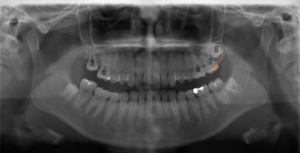

(治療前:写真左)

上顎右側第二大臼歯(7)がなくなってから時間がたっており、第三大臼歯=親知らず(8)が前の歯に近づいてきています。

(治療後:写真右)

上顎左右ともに第二大臼歯(7)ではなく、第三大臼歯=親知らず(8)を咬み合わせに参加させ、安定した、咬合再構成を行いました。